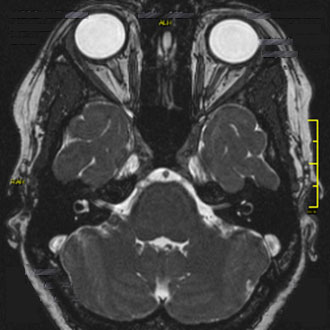

Bei Beschwerden im Bereich der Augen oder Sehstörungen liefert die MRT der Orbita wertvolle Einblicke in die Strukturen von Sehnerv, Augenmuskeln und umliegendem Gewebe.

Sie wird häufig eingesetzt zur Diagnose von Sehnerventzündungen (Opticusneuritis), die oft im Zusammenhang mit Multipler Sklerose auftreten, oder bei endokriner Orbitopathie (Morbus Basedow). Auch Tumoren wie das Opticus-Meningeom oder Fehlstellungen der Augenmuskulatur können mit der MRT präzise beurteilt werden.